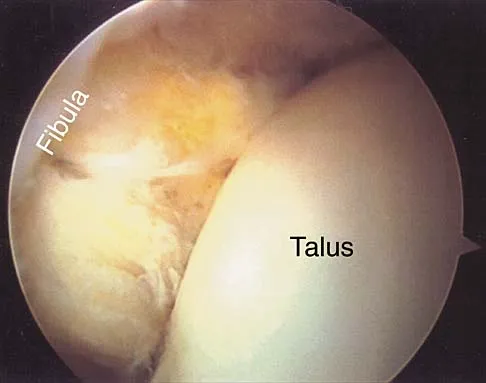

Figure 7 shows the MRI scan of a 23-year-old competitive rugby player who has anterior ankle pain and swelling. He states that he has been playing for many years and has sprained his ankle several times. Examination will reveal what specific hallmark feature?

Detailed Explanation